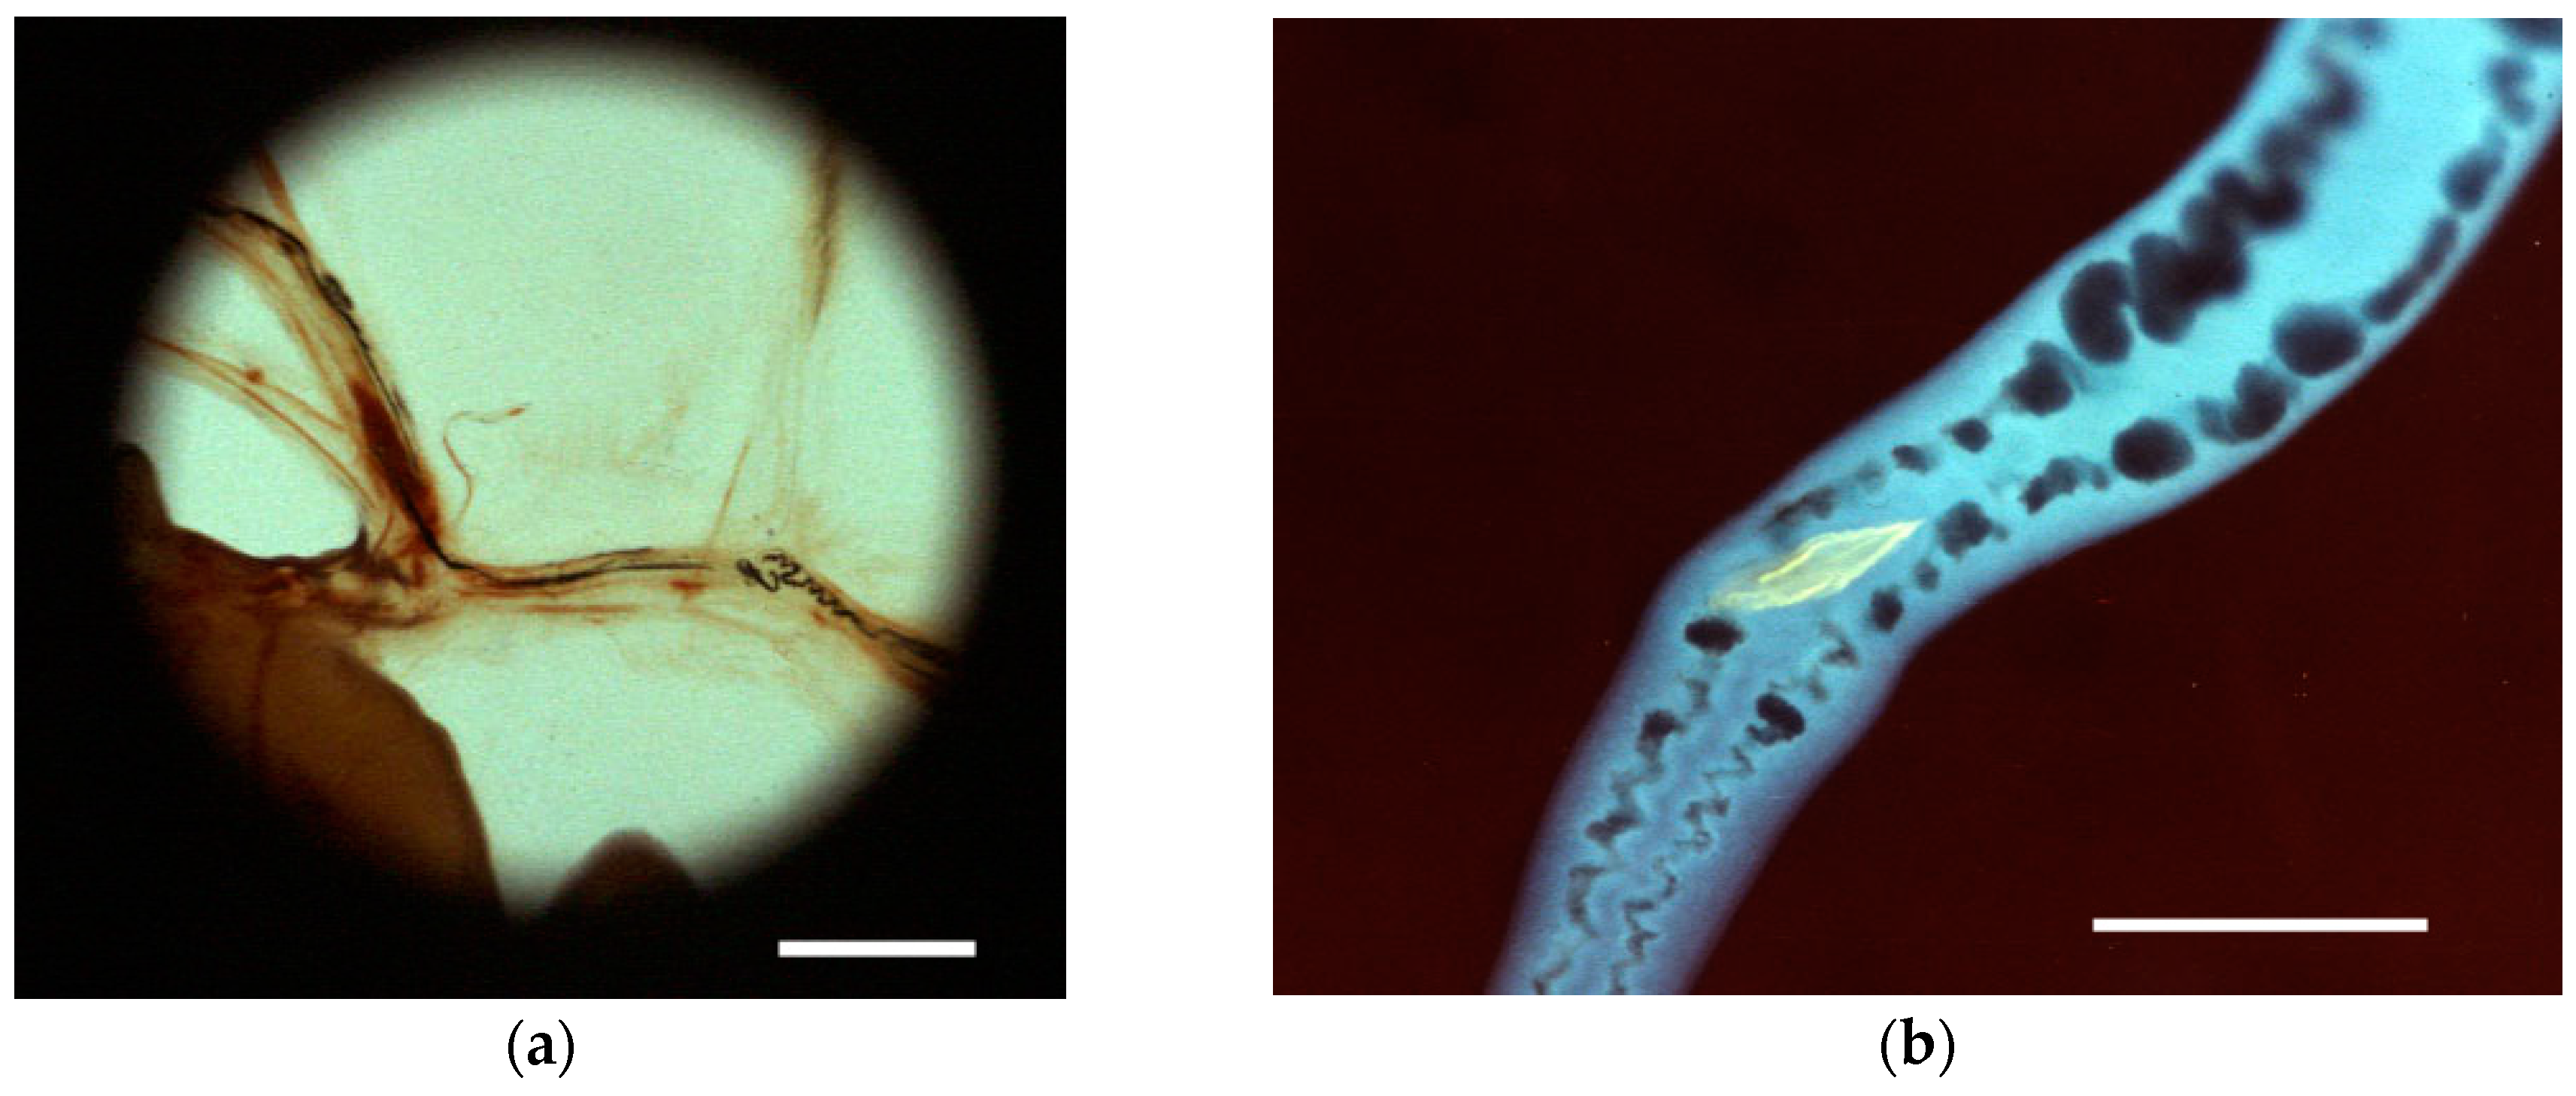

3.1.2. Cercaria

- Linder, E. Fluorochrome-labelled lectins reveal secreted glycoconjugates of schistosome larvae. Parasitol. Today 1986, 2, 219–221. [Google Scholar] [CrossRef]

- Linder, E.; Thors, C.; Lundin, L. Isolation of an SBA lectin-reactive glycoprotein (GP50) and its identification in Schistosoma mansoni larval and adult worm secretions. J. Parasitol. 1991, 77, 391–401. [Google Scholar] [CrossRef] [PubMed]

- Thomas, A. Aquatics under Polarization. Available online: http://www.microscopy-uk.org.uk/mag/artdec11/tt-pol-aquatic.pdf (accessed on 6 June 2016).

- Linder, E. Cercarial kissing marks-no superficial make-up. Parasitol. Today 1990, 6, 393–395. [Google Scholar] [CrossRef]

| Attachment/Penetration into host | Wiggling/Tail loss/ | Video S3; Figure 3b | |||

| Inchworm | - | ||||